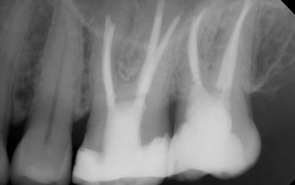

Weil es bei der Wurzelbehandlung um sehr kleine Größenverhältnisse geht, hat sich das Dentalmikroskop als Hilfsmittel durchgesetzt. Dies bedeutet, das die gesamte Wurzelbehandlung durch den ausgebildeten Spezialisten bei 10 - 30 facher optischer Vergrößerung durchgeführt wird. Zusätzlich kommt eine spezielle Beleuchtung zum Einsatz.

- Das Dentalmikroskop macht Wurzelkanäle für den Zahnarzt sichtbar, die ohne Mikroskop nicht zu sehen und deshalb auch nicht zu behandeln sind.

- Das Auffinden und die Entfernung von frakturierten Instrumenten wird wesentlich erleichtert.